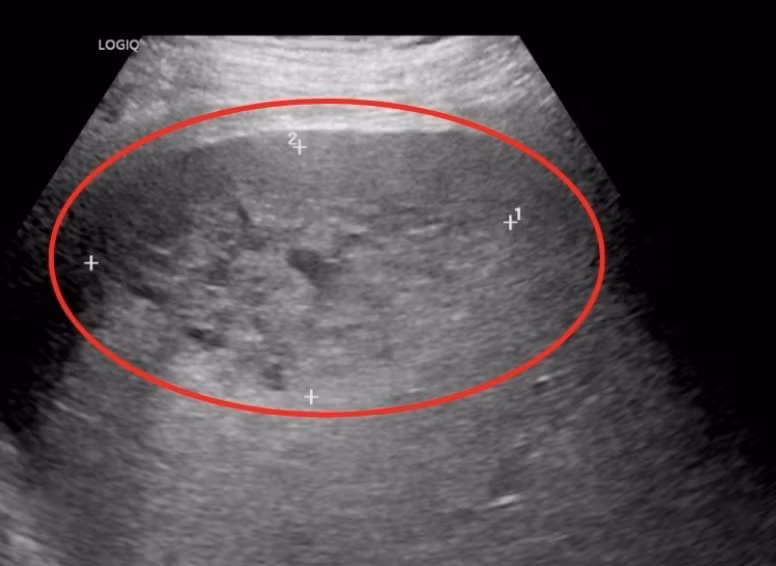

Qua siêu âm ổ bụng, các bác sĩ ghi nhận gan của ông T. to bất thường. Tại thùy gan phải xuất hiện vùng tổn thương lớn sát bao gan, gồm nhiều nang nhỏ kèm viền thâm nhiễm rộng xung quanh. Hai tổn thương chính có kích thước lần lượt 52×88 mm và 25×32 mm. Ngoài ra, bệnh nhân còn có tình trạng dịch ổ bụng và dịch màng phổi.

Ổ áp xe chiếm gần trọn gan phải đẩy người bệnh vào cơn nguy kịch - Ảnh BVCC

Bệnh nhân H. được xác định nhiễm khuẩn huyết nặng do ổ áp xe gan kích thước lớn, diễn tiến đến sốc nhiễm khuẩn và suy đa cơ quan, tình trạng đặc biệt nguy kịch.

PGS.TS.BS Nguyễn Cảnh Bình, Trưởng khoa Tiêu hóa, Bệnh viện Đa khoa Hồng Ngọc – bác sĩ trực tiếp điều trị cho bệnh nhân H. cho biết: “Ổ áp xe có kích thước rất lớn, gần như chiếm toàn bộ gan phải, trong khi ranh giới bên ngoài của khối áp xe nằm sát vỏ gan nên nguy cơ chảy máu hoặc vỡ ổ áp xe là rất cao.

Đáng chú ý, tại thời điểm cấp cứu, tình trạng viêm từ ổ áp xe đã lan thấm ra ngoài, gây tràn dịch màng bụng và tràn dịch màng phổi, khiến diễn biến bệnh trở nên hết sức nghiêm trọng”.